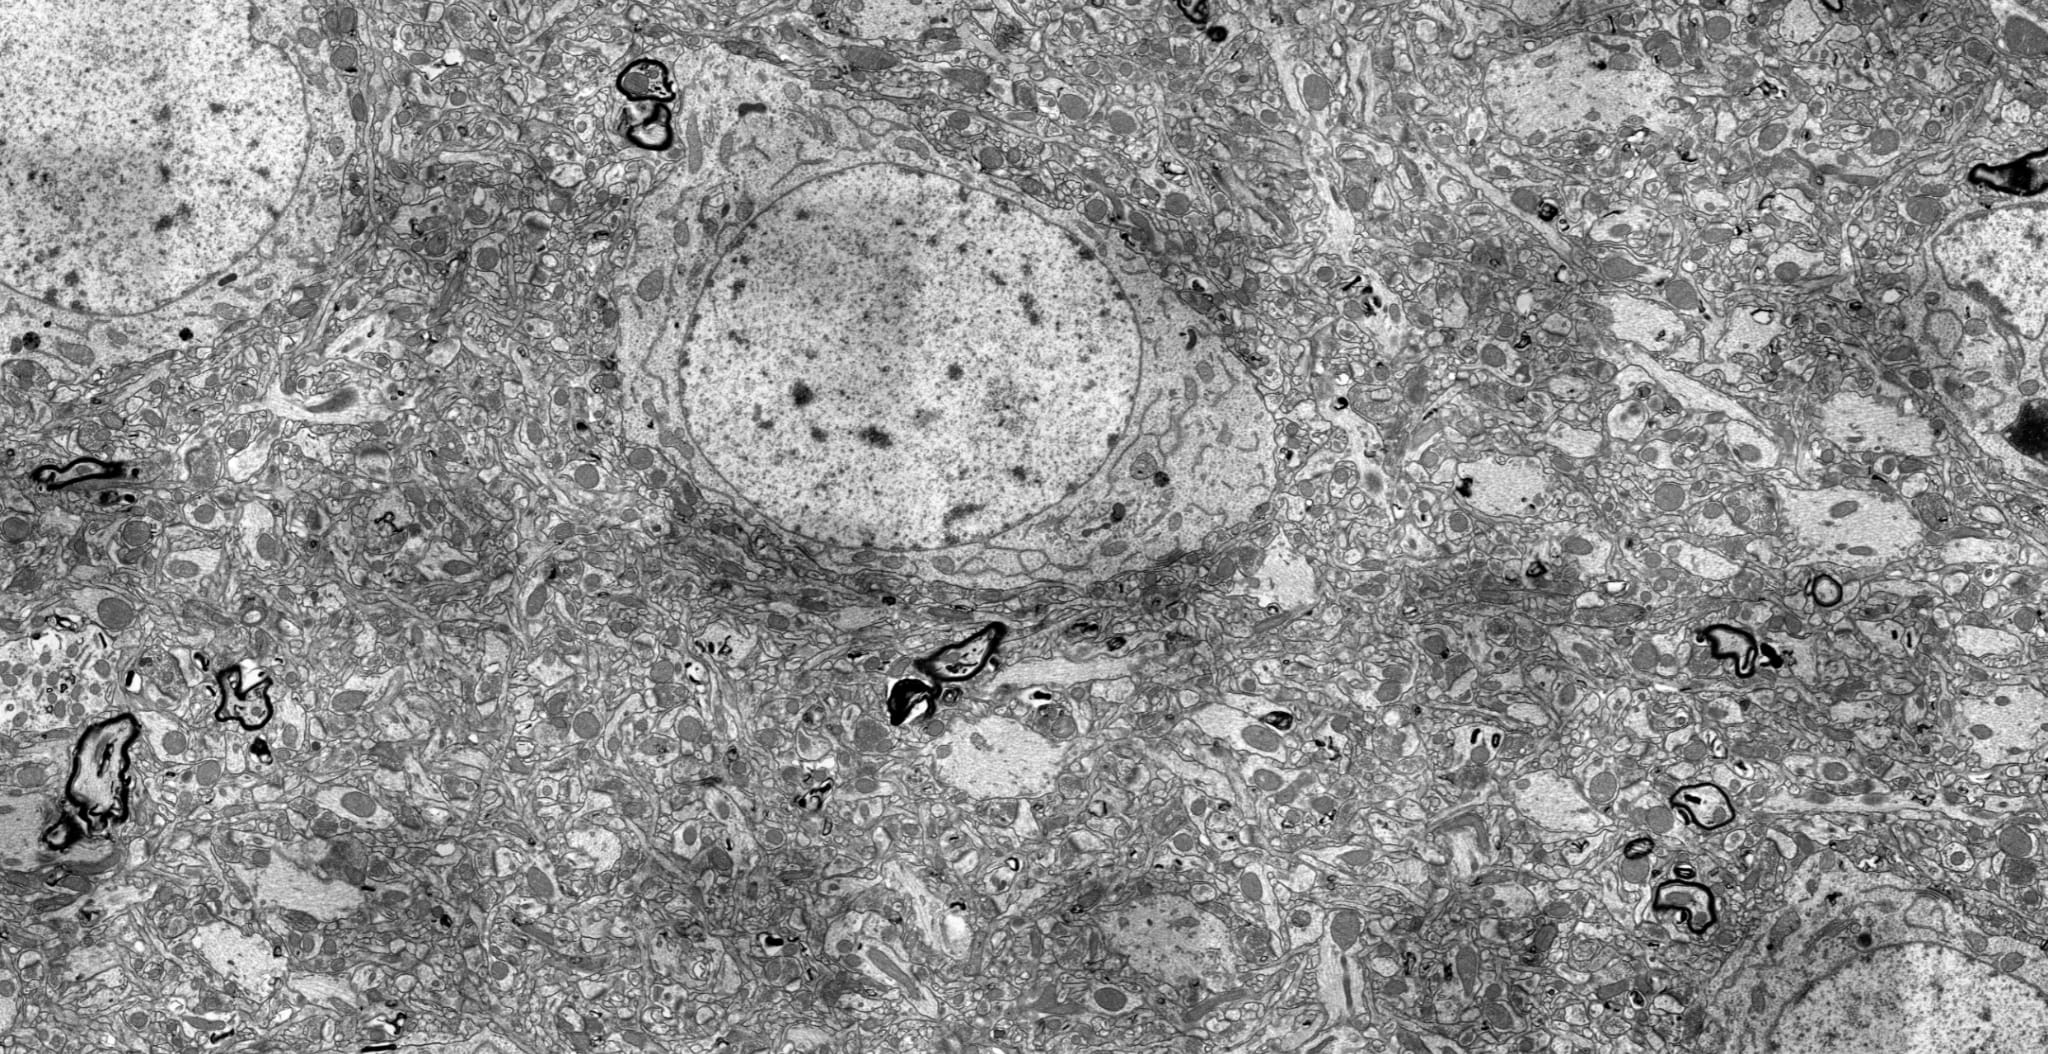

The images above are taken from the BPF’s Accreditation page. On the left, you can see the pig brain which I preserved, winning the Large Mammal prize. The cellular structure is intact and it’s easy to trace the connections between the neurons. The right-hand image shows the damage caused by traditional cryopreservation, even under ideal circumstances. Real preservation cases are far worse due to pre- and post-mortem brain damage. Maybe a superintelligence could reconstruct the structure – but it’s unclear whether the information to do so remains.

This is a section taken from a rat brain preserved 5 minutes post-mortem in a manner that’s consistent with the surgical time we can achieve with pigs. All axons, dendrites, and synapses pictured are connectomically traceable. After preservation, we stored this brain at 60°C for ~12 hours before imaging! Click through for a “Google Earth”-style presentation of the whole slice, which is around 5 GB of data.